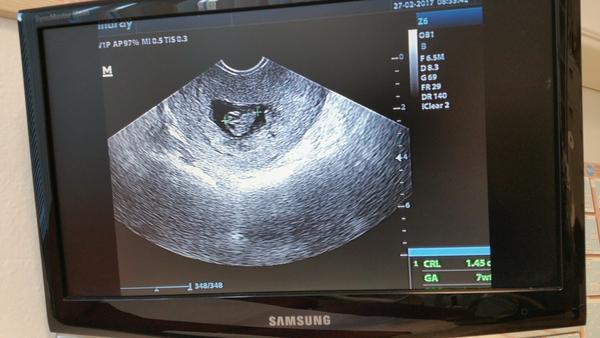

@slniecko26 prekrásny obraztek 😍😍😍obrovská gratulácia 😘😘

@slniecko26 krásna fotka mi ideme vo štvrtok na kontrolu dúfam že aj ja budem mať takú peknú 😍